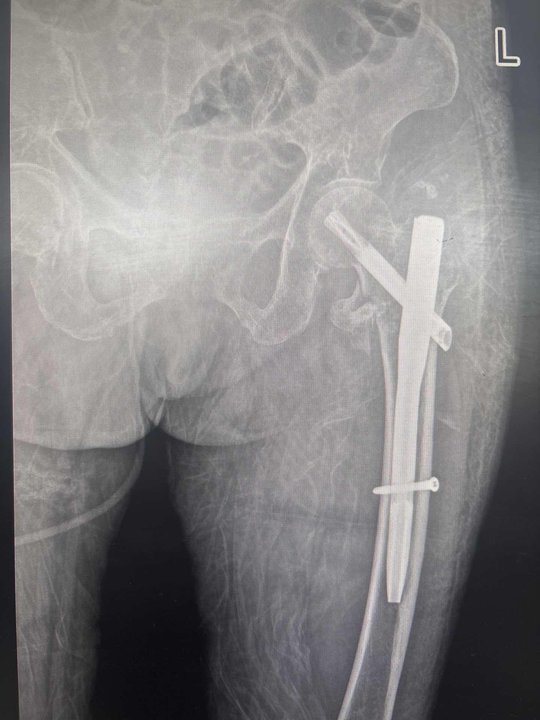

手术后

积极完善相关检查,排除手术禁忌,经并向患者告知病情,征求同意后,科室开通老年髋部骨折绿色通道,并于48小时内,在麻醉手术科配合下,为这位高龄老人行左侧股骨转子间骨折闭合复位髓内钉内固定术。手术顺利完成,患者安返病房,给与消炎止痛、消肿、营养支持、促进骨折愈合等对症治疗后,患者转入全科医学科进行救治,目前已康复出院。